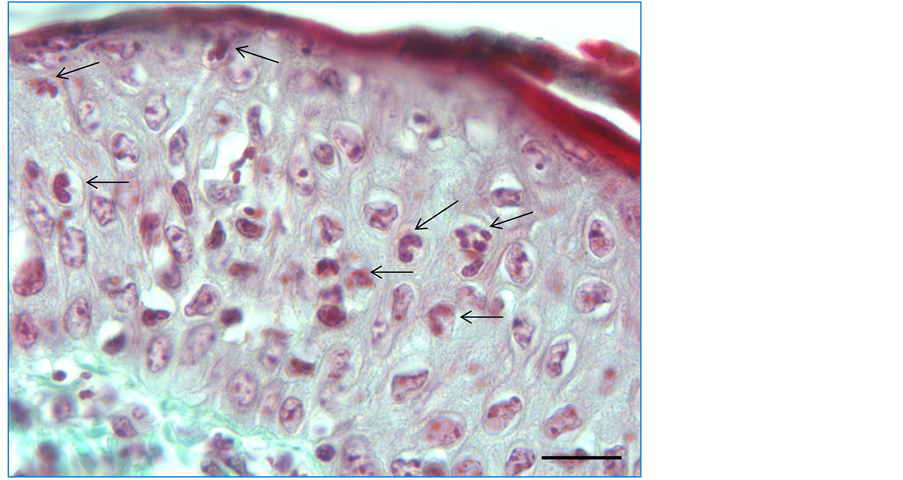

Histopathologically, macroscopic evaluation of the collected parts of the skin showed no changes. The skin was clear, no swelling, blisters or erosions. In the studied parts of the skin there were no skin lesions typical for inflammation. Neutrophil mobilization was observed mainly in the dermis. In three cases (1 in the propolis group, 2 in the Balsam of Peru group) numerous mast cells in the field of view in the dermis were observed. Most of them were situated below the epidermis and around the capillary (Figure 1(a)) and around the blood vessels in the deeper layers of the dermis (Figure 1(b)).

In other cases, the granulocytes were few or a single in the field of view. Only in one case of the propolis group, numerous neutrophils and monocytes infiltrated epidermis (Figure 2).

Figure 1. (a) (b) Cross section through the skin of guinea pig (group of propolis) with numerous mast cells (↓) under epidermis (a) and around capillaries (b). Staining with May-Grunwald Giemsa. Scale bar 20 μm.